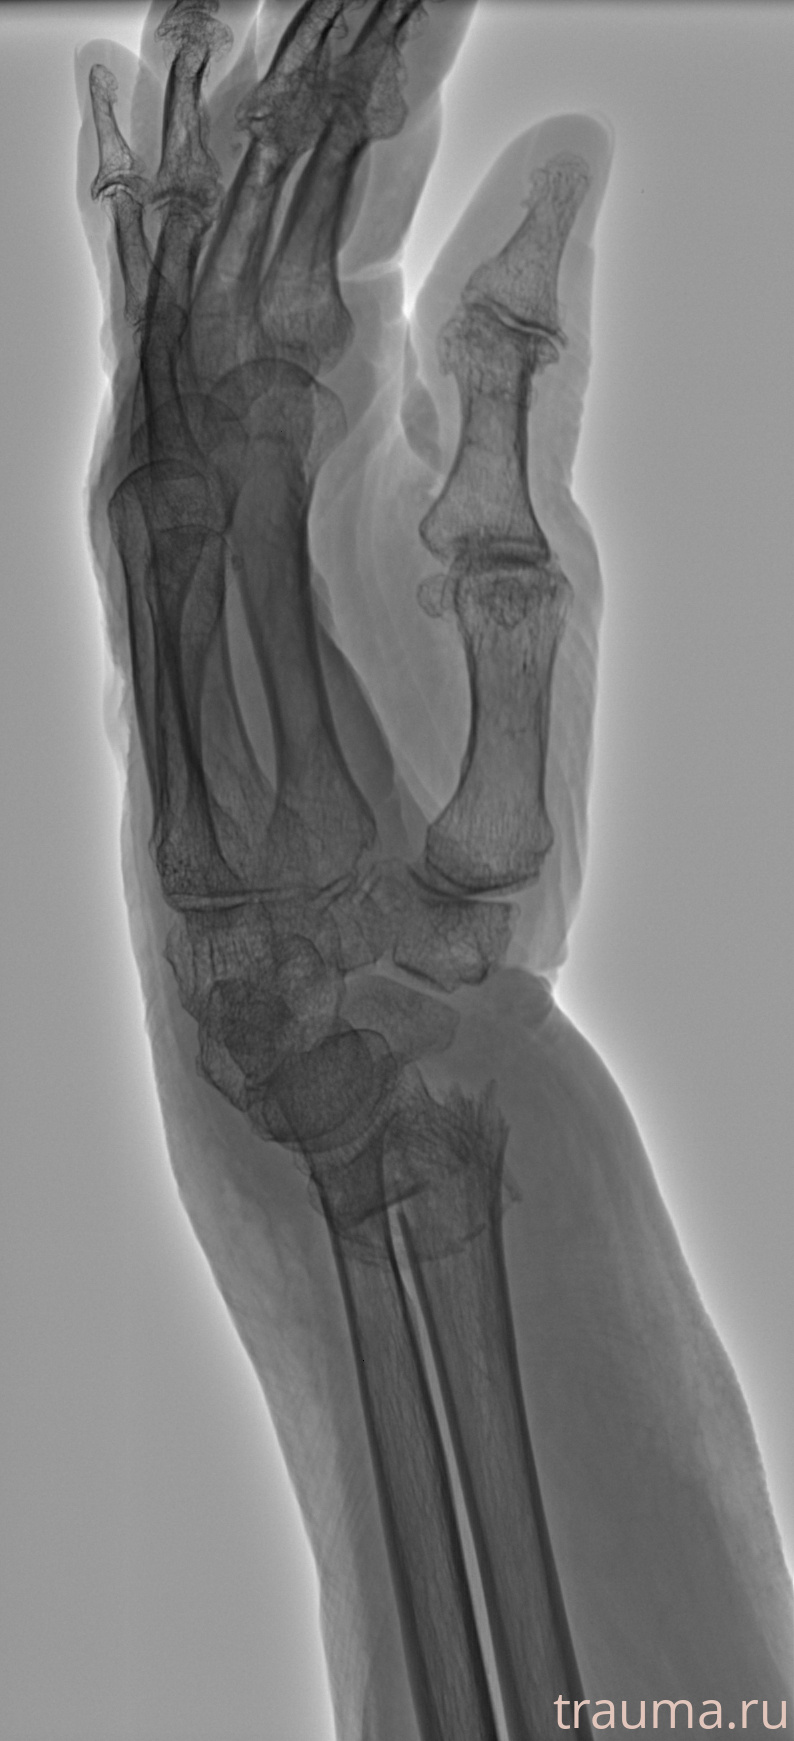

Рентгенограммы

Рентген на дому: по вашему адресу приезжает врач-рентгенолог, травматолог-ортопед с мобильным рентгеновским аппаратом, проводит диагностику травмы или заболевания, делает необходимые рентгенограммы, дает рекомендации по дальнейшему лечению. Получить качественные снимки в домашних условиях возможно благодаря уникальной методике, разработанной МосРентген Центром для института  Склифосовского